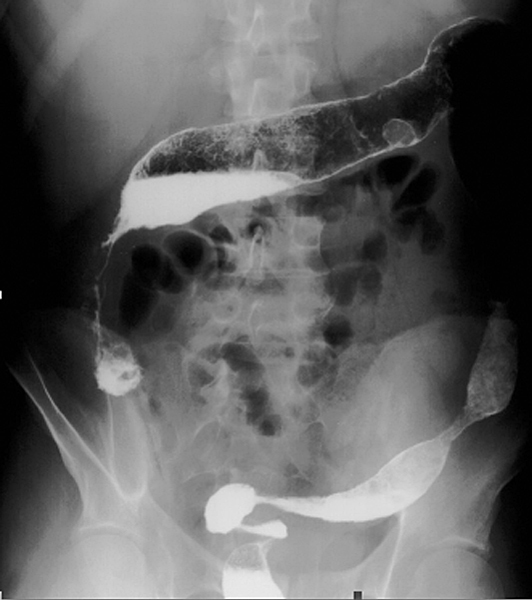

Sténose compliquant l'évolution d'une maladie de Crohn et correspondant à un adénocarcinome colique après analyse histologique de la pièce opératoire.